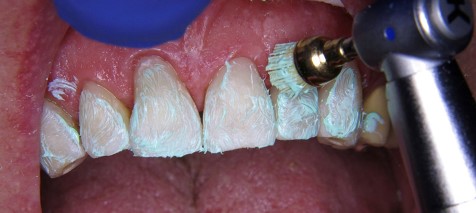

Do polerowania na wysoki połysk zastosowano impregnowane diamentami gumki polerskie Dimanto (VOCO GmbH, Cuxhaven) z prędkością 5000 obrotów na minutę przy chłodzeniu strumieniem wody i ograniczonym nacisku podczas pracy. Na zakończenie wypolerowano zęby drobnoziarnistą pastą polerską Cleanjoy (VOCO GmbH, Cuxhaven), również wywierając niewielki nacisk (ryc. 14).

Ryc. 14. Ostateczne polerowanie zęba i powierzchni wypełnień.